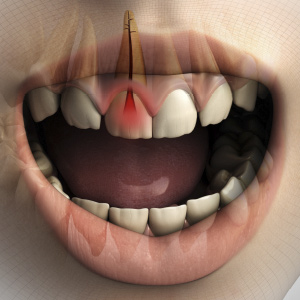

New Directions in Endodontics

This Compendium eBook features a continuing education (CE) article on the management of endodontic flare-ups. This eBook also includes an article on intentional replantation as a predictable and cost-effective option for preserving a natural tooth and as a favorable alternative to conventio...

Breakthroughs in Endodontics

This Compendium eBook offers a continuing education (CE) article on the critical decision-making process involved in determining whether to restore or replace compromised maxillary anterior teeth, with an emphasis on the importance of timely treatment decisions and their criteria. In addit...